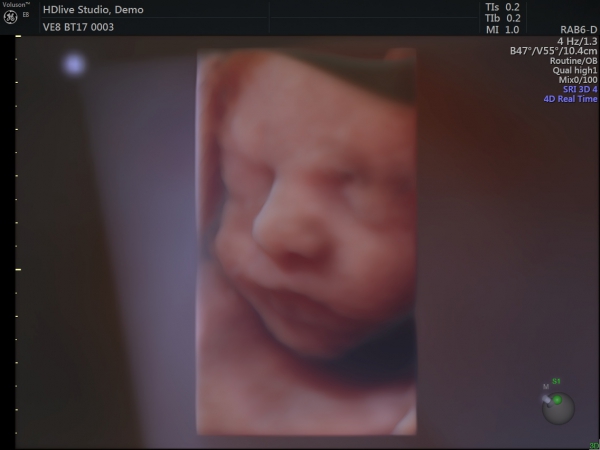

سونوگرافی NT (غربالگری مرحله اول)

سونوگرافی آنومالی اسکن (غربالگری مرحله دوم)

اکوی قلب جنین

حاملگی (بررسی سه ماهه سوم)